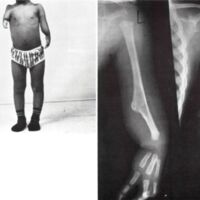

Fig. 6. Left, monodigital ulnar hemimelia, incomplete. Right, X-rays reveal proximal remnant of the ulna with a bowed radius.

Incomplete ulnar hemimelia occurred twice in this series. The proximal portion of the ulna is present, thus affording a normal-appearing elbow joint with an excellent range of motion (see Fig. 6). That child was seen at four years of age and fitted with a standard below-elbow prosthesis, which she is currently wearing.